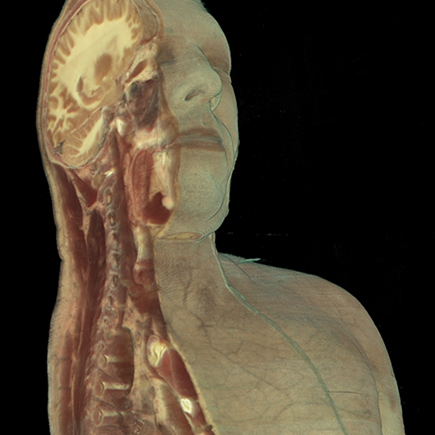

A 3D View Into the Body

One of the most intriguing uses of GPUs is its application to data sets that represent the human body. Divvied up into high-resolution, 3D slices by imaging devices such as CT, ultrasound and MRI scanners, the body amounts to gigabytes upon gigabytes of data that offers doctors and medical researchers an unprecedented view into the human form. Processed by GPU-powered algorithms, this immense amount of data can provide doctors a realistic 3D view of a beating heart within a patient's chest or the real-time brain activity of a stroke victim, facilitating faster, better diagnoses.

Medical students at the New York University School of Medicine wear NVIDIA 3D Vision glasses to dissect virtual cadavers projected onto screens, with different parts and systems of the body brightly colored for identification. Forensic scientists are experimenting with similar technologies for use during autopsies to unobtrusively determine the cause of death of individuals. The future promises animated, searchable anatomical maps that doctors, researchers and laypeople alike can use as easily as online street maps.